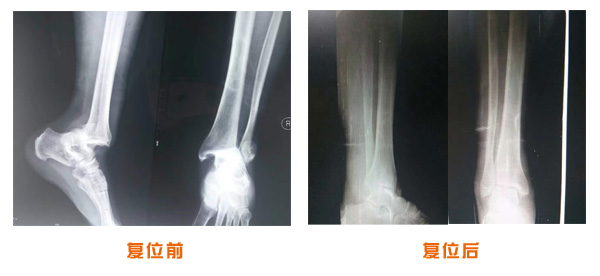

肥城市安駕莊梁氏骨科醫(yī)院是一所以梁氏手法正骨配合膏藥為特色的現(xiàn)代化專科醫(yī)院。

梁氏骨科術始創(chuàng)于清雍正年間,歷經(jīng)八代,至今已有三百年歷史。據(jù)1929年泰安縣志載“梁瑞圖先生,字增生,號蓮峰,安駕莊人,精岐黃并發(fā)明接骨,凡跌打車凡跌打車軋皮不破而碎骨者......【詳細】 |